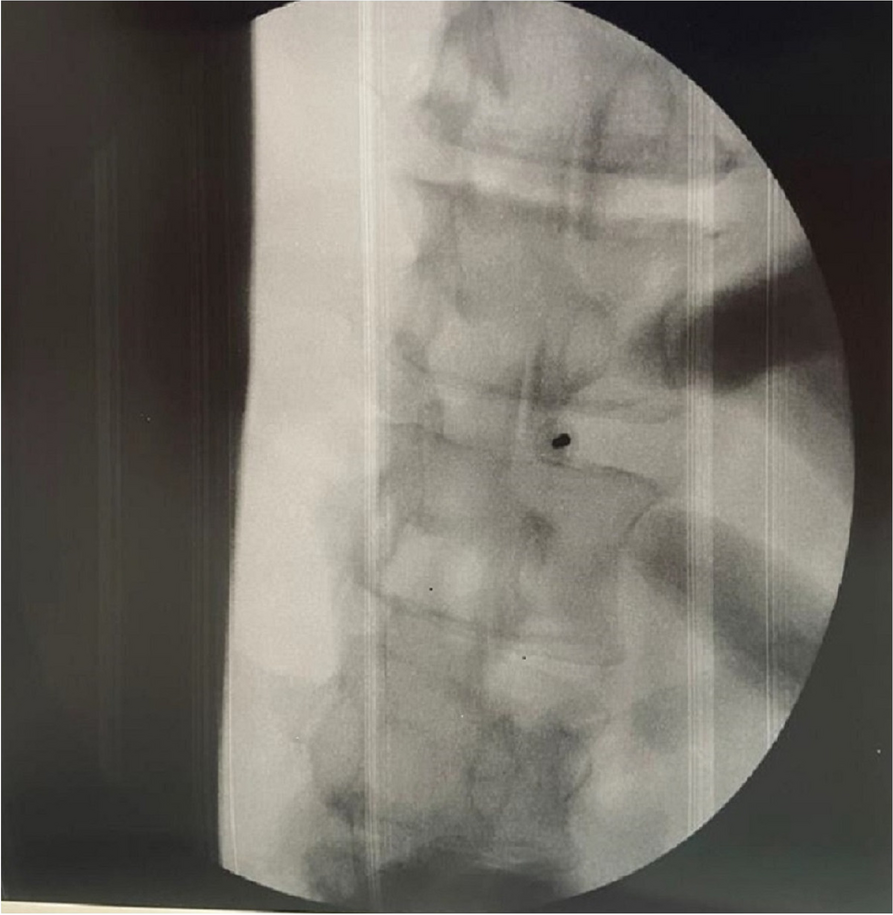

A21 Postoperative severe acute pancreatitis after propofol anesthesia: a case report

T.A. Giacon 1, F. Carbotti 1, N. Asti 1, I. Scarpone 1, L. Troisi 1, S. Congedi 1, A. Boscolo 1, T. Pettenuzzo 1, P. Navalesi 1, M. Meggiolaro 2

1 Institute of Anaesthesia and Intensive Care Unit, Padua University Hospital,, Padova, ITALY; 2 Anaesthesia and Intensive Care Unit, Ss. Giovanni e Paolo Hospital, Venezia, Italy

Correspondence: T.A. Giacon

Journal of Anesthesia, Analgesia and Critical Care 2023, 3(Suppl 1):A21

CASE REPORT

A 75 years old patient whose characteristics are reported in Table 1 was admitted for a programmed laparotomic radical cystectomy due to bladder cancer.

General anesthesia was obtained with target controlled infusion (TCI) of Propofol with Eleved Model [1], TCI of Remifentanil [2], Midazolam, Ketamine and Rocuronium. Other drugs administered are reported in table 1. The patient remained normothermic and hemodynamically stable, even though due to blood loss > 1 l and anemization he was transfused.

At awakening the patient was extubated and transferred to the intensive care unit (ICU) for postoperative monitoring with optimal haemodynamic, neurological and antalgic control.

A few hours after the admission in ICU he reported a blunt abdominal pain, mainly on the right side, nausea and the exams showed increased amylase levels, urologists excluded any surgical involvement of pancreatic tissue and suspected a transient sphincter of Oddi dysfunction [3]. After one night in ICU he was transferred to the urology ward due to his clinical stability, even though Amylase peaked at 2340 U/l. Two days later abdominal pain increased to severe, with characteristics of peritonism and increased inflammatory markers. An abdomen-thorax CT scan revealed acute pancreatitis (AP) (Figure 1) and he was transferred to ICU. He started a standard treatment for acute pancreatitis and antibiotic therapy [4].

On postoperative day nine, due to general deterioration of clinical conditions and further anemization that required blood transfusion, he underwent an emergency laparotomy, in which propofol was not used as an anesthetic drug, that found a completely necrotic pancreas. The following day he faced a multi organ failure (MOF) which rapidly led to death. Consent to publish the case report was accorded by the family.

Acute pancreatitis (AP) Is a complex and severe disease with a high mortality rate [4]. Propofol, is a common anesthetic drug which is widely used in daily practice for sedations and general anesthesia [5], few cases of Propofol Induced AP have been published, in which the diagnosis has been made excluding more common causes [6].

In fact, Propofol is listed as a possible cause of AP, class Ib, based on the classification of Badalov et al. [7]. Following the scheme proposed by the systematic review by Haffar et al for Propofol induced AP [6] we could confirm that our hypothesis is plausible. He satisfied the American College of Gastroenterology criteria for AP [8,9] and it is classified as severe acute pancreatitis according to the Revised Atlanta Classification with peripancreatic necrotic fluid collection [10]. Marshall score [11] after admission was two and Naranjo et al [12] probability scale for drug adverse reaction was three, meaning that the adverse reaction is possible. Latence according to Badalov et al [7] has been short or intermediate. Exclusion of other plausible causes, timing of pancreatitis symptoms and previous cases in literature support our hypothesis of propofol induced pancreatitis.

Informed consent to publish had been obtained.

Fig. 1 (abstract A21).

See text for description

Bild vergrößern